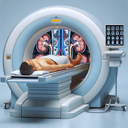

Магнітно-резонансна томографія (МРТ) органів черевної порожнини — це неінвазивний метод візуалізації, який використовує магнітне поле і радіохвилі для отримання детальних зображень внутрішніх органів та структур. Це дослідження допомагає лікарям виявляти й діагностувати різноманітні захворювання й патології, такі як пухлини, запальні процеси, камені в жовчному міхурі, ураження печінки та інші. Ось чому МРТ органів черевної порожнини важливе: 1...

Магнітно-резонансна томографія (МРТ) малого тазу у чоловіків є неінвазивним методом діагностики, що дозволяє отримати детальні зображення тканин та органів без застосування рентгенівського випромінювання. Це дослідження може бути приписане для оцінки різних станів або патологій. ### Основні показання для МРТ малого тазу у чоловіків: - Підозра на новоутворення (доброякісні чи злоякісні) - Оцінка стану простати - Виявлення метастазів при відомому онкологічному процесі - Діагностика запальних процесів - Оцінка травм тазової ділянки ### Переваги МРТ: - Висока роздільна здатність зображень - Безпечний метод без використання іонізуючого випромінювання - Можливість детальної оцінки м’яких тканин ### Процедура: - Пацієнт лягає на спеціальну поверхню, яка переміщується в магнітний тунель...